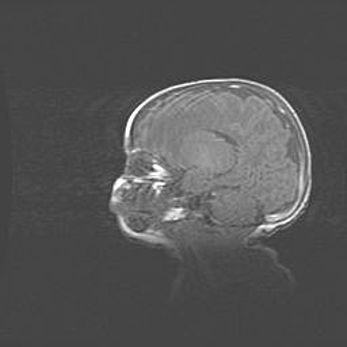

Лейкомаляция с кистозно-глиозной дегенерацией головного мозга.

Возраст: 2 месяца 25 дней

Вес: 6400 г

Окружность головы: 40 см

Срок гестации: 41 неделя

Лейкомаляцию относят к ишемически-гипоксическим повреждениям головного мозга, диагностируемым у новорожденных. При лейкомаляции в головном мозге обнаруживают очаги некроза, возникшие после тяжелой гипоксии и нарушения кровотока. В процессе морфогенеза очаги проходят три стадии: 1) развития некроза, 2) резорбции и 3) формирования глиозного рубца или кисты. Перивентрикулярная лейкомаляция (ПЛ) встречается примерно в 12% случаев среди новорожденных, обычно – у недоношенных детей, причем, частота ее зависит от массы, с которой младенец появился на свет. Наибольшее число малышей страдает лейкомаляцией, если масса при рождении 1500-2500 г.